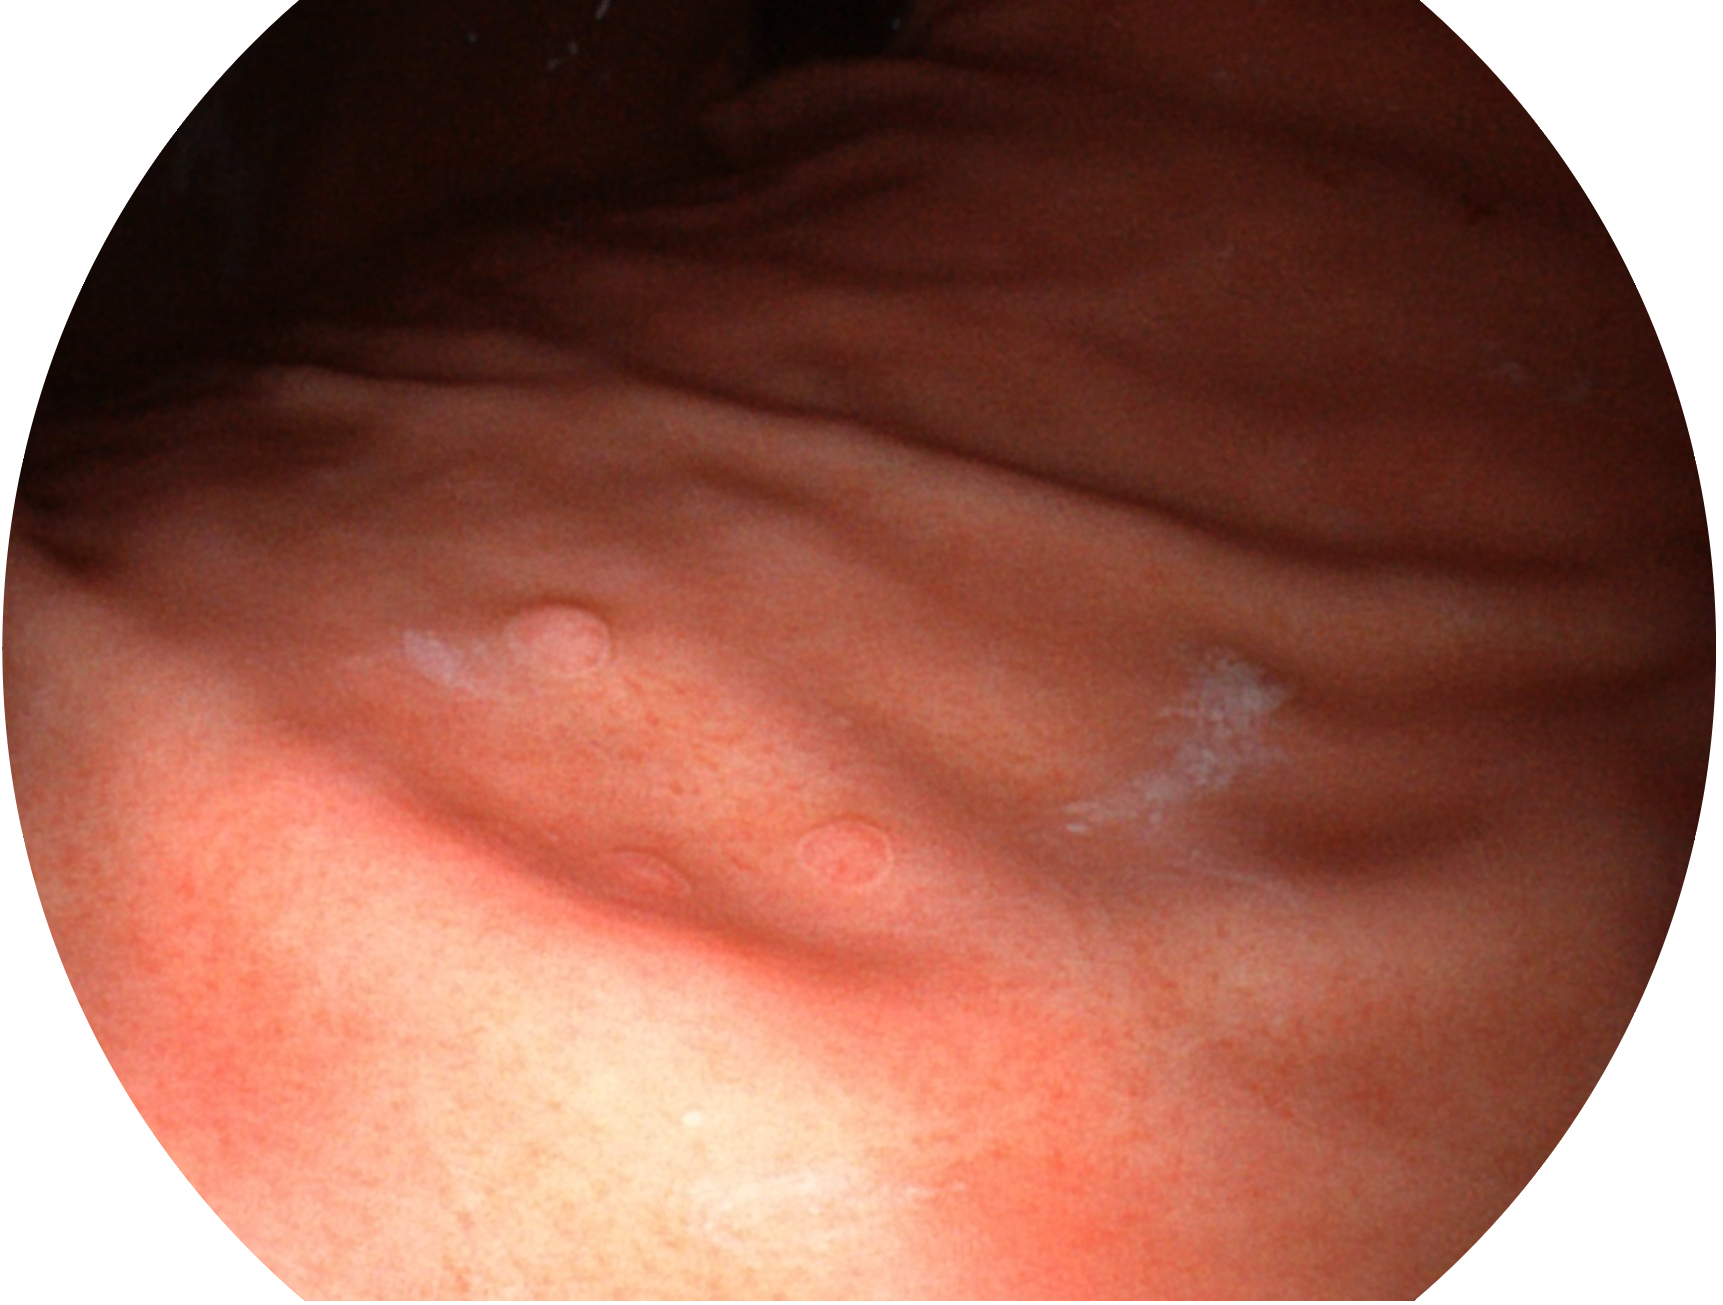

DB中国旗舰官方网站新开发的内镜染色技术,主要是基于多波长LED 光源的开发,VLS-55Q 四波长LED 光源是由四个不同颜色的LED光按照相应照明模式所规定的特定发光比例进行合束后形成,合束后形成的照明光的光谱由红光、绿光、蓝光及蓝紫光这四个不同的波段范围构成。具有更高光谱自由度,通过光谱比例的控制,实现了聚谱成像技术,英文全称为“Spectral Focused Imaging, SFI”,缩写为“SFI”和光电复合染色成像技术,英文全称为“Versatile Intelligent Staining Technology, VIST”,缩写为“VIST”。